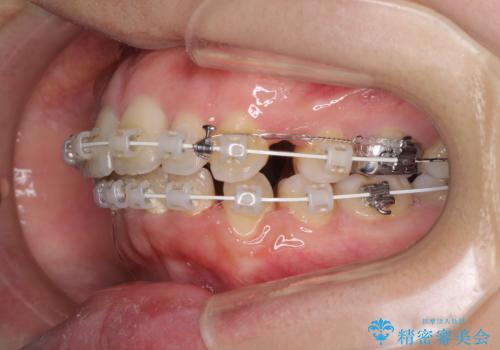

- 前歯のデコボコと口元の突出感を気にして来院された患者様です。

上下左右第一小臼歯4本を抜歯し、ワイヤー装置にて口元を引っ込めるよう矯正治療を行うこととしました。

叢生が強かったため、口元の突出感の改善には限界がありましたが、横側からも口元が引っ込んだ感じが分かるほど改善されました。